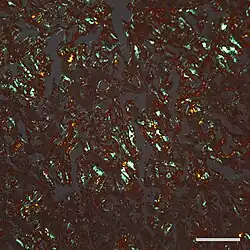

| Micrograph of a section of the cerebral cortex from a person with Alzheimer's disease, immunostained with an antibody to amyloid beta (brown), a protein fragment that accumulates in amyloid plaques and cerebral amyloid angiopathy. 10X microscope objective. |

The concept of proteopathy can trace its origins to the mid-19th century, when, in 1854, Rudolf Virchow coined the term amyloid ("starch-like") to describe a substance in cerebral corpora amylacea that exhibited a chemical reaction resembling that of cellulose. In 1859, Friedreich and Kekulé demonstrated that, rather than consisting of cellulose, "amyloid" actually is rich in protein.[9] Subsequent research has shown that many different proteins can form amyloid, and that all amyloids show birefringence in cross-polarized light after staining with the dye Congo red, as well as a fibrillar ultrastructure when viewed with an electron microscope.[9] However, some proteinaceous lesions lack birefringence and contain few or no classical amyloid fibrils, such as the diffuse deposits of amyloid beta (Aβ) protein in the brains of people with Alzheimer's.[10] Furthermore, evidence has emerged that small, non-fibrillar protein aggregates known as oligomers are toxic to the cells of an affected organ, and that amyloidogenic proteins in their fibrillar form may be relatively benign.[11][12]